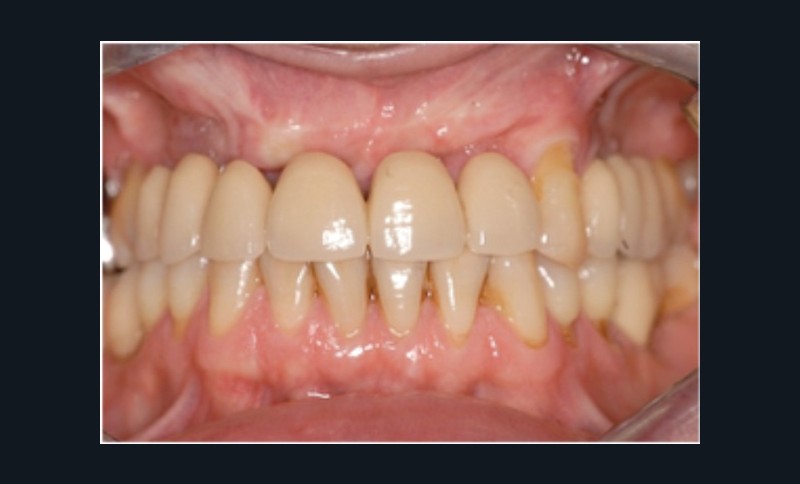

Cette partie de la présentation ne se contentait pas de rapporter les principes précédemment décrits à des régions limitées des maxillaires mais étendait la discussion à la difficulté majeure rencontrée en implantologie : rattraper des erreurs de positionnement implantaire ayant entraîné des compromis prothétiques inesthétiques. La solution thérapeutique mise en œuvre par Benoît Philippe consiste à appliquer la procédure d’ostéotomie segmentaire à l’entité constituée par l’os alvéolaire péri-implantaire et les implants. Les couronnes implantaires sont déposées. Le tracé d’ostéotomie encadre le segment à repositionner mais n’implique pas la corticale palatine qui sera fracturée pour éviter toute lésion du périoste (nourricier du segment alvéolo-implantaire). Un dispositif prothétique préparé en amont guide la translation du fragment qui est fixé au moyen de plaque d’ostéosynthèse dans la situation idéale. Le capital squelettique est reconstruit et l’espace prothétique disponible est normalisé.

Au cours de la conférence, Benoît Philippe a énoncé ses convictions concernant les conditions de succès du traitement implanto- prothétique : le respect d’une biomécanique implantaire équilibrée, le recours à des implants plus fins et moins nombreux que ne l’imposaient les préconisations d’autrefois, l’observation du biotype parodontal plus ou moins favorable aux reconstructions des atrophies étendues, la nécessité de restaurer au préalable puis de maintenir un environnement parodontal satisfaisant (en particulier la gencive attachée péri-implantaire).